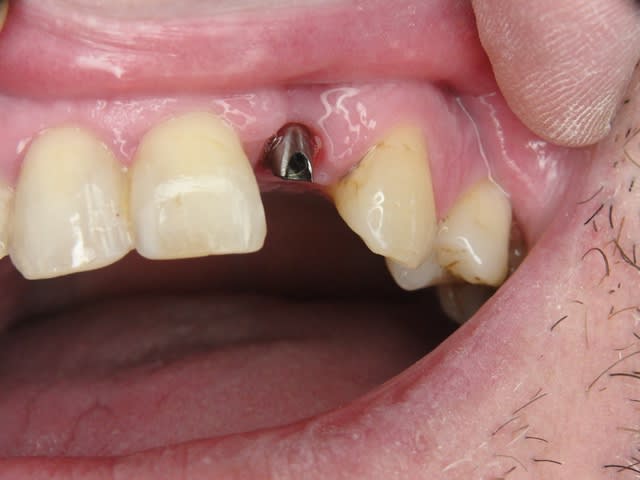

Photos d'un cas d'extraction implantation immédiate, stabilité primaire (de mémoire) assez élevée.. 60/70 N ..démontage du gingiva clips et du shuttle, pilier serré 40N, couronne procera

La pose de la couron nec'est faite 8 semaines apres l'extraction implantation immédiate, la particularité de ce systeme permet de ne pas démonter le shuttle ni la gingivaclip pour l'empreinte..je pense que ca aide bien à la qualité gingivale...radio controle ci jointe